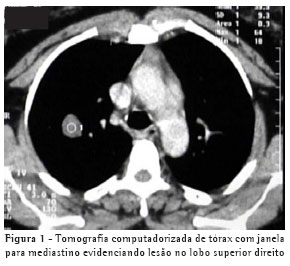

O exame físico apresentou-se normal e os seguintes exames complementares foram realizados: telerradiografia de tórax, tomografia computadorizada de tórax, espirometria, intradermorreação para tuberculose (PPD), sorologia para Aspergillus, broncofibroscopia com lavado broncoalveolar e escovado brônquico do segmento direito. A telerradiografia de tórax evidenciou imagem nodular de contornos regulares em topografia do terço superior do hemitórax direito. A tomografia computadorizada de tórax (Figura 1) evidenciou nódulo de contornos regulares, medindo 2 cm, localizado no segmento apical do lobo superior direito. O referido nódulo tinha impregnação pelo contraste, com aumento de 26,7 unidades Hounsfield após três minutos da injeção do contraste venoso, e área central de aparente cavitação. As análises do lavado broncoalveolar e escovado brônquico foram negativas para neoplasia, pesquisa de bacilo álcool-acidorresistente e cultura para tuberculose, fungos e bactérias.

Freqüentemente, o achado na radiografia de tórax mostra-se como um nódulo solitário e bem delimitado.(2) A tomografia computadorizada da paciente mostrou um nódulo bem definido com aumento de 26,7 unidades Hounsfield após impregnação pelo contraste (Figura 1). Um estudo definiu que 98% dos nódulos benignos apresentavam realce pelo contraste de 15 unidades Hounsfield ou menos.(7) No presente caso, a utilização de contraste na tomografia não seguiu as recomendações desse estudo e a impregnação do contraste não pode, portanto, ser considerada desta forma. Outros autores, em relato de caso sobre o adenoma alveolar, não encontraram impregnação do nódulo pelo contraste, confirmando a natureza benigna do mesmo.(4)